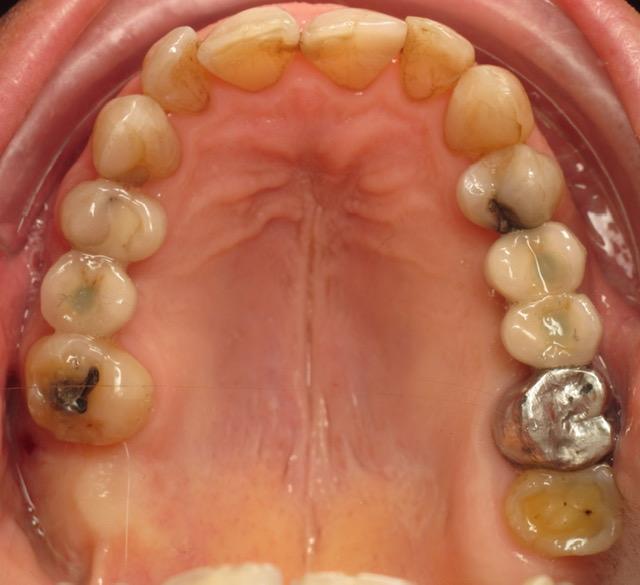

Cas 2 : redressement molaire maxillaire

Utilisation d’un sectoriel à action linguo-vestibulaire pour correction transversale prémolaire. Arc rond stabilisé par minivis en utilisant l’œillet de la tête de la minivis.